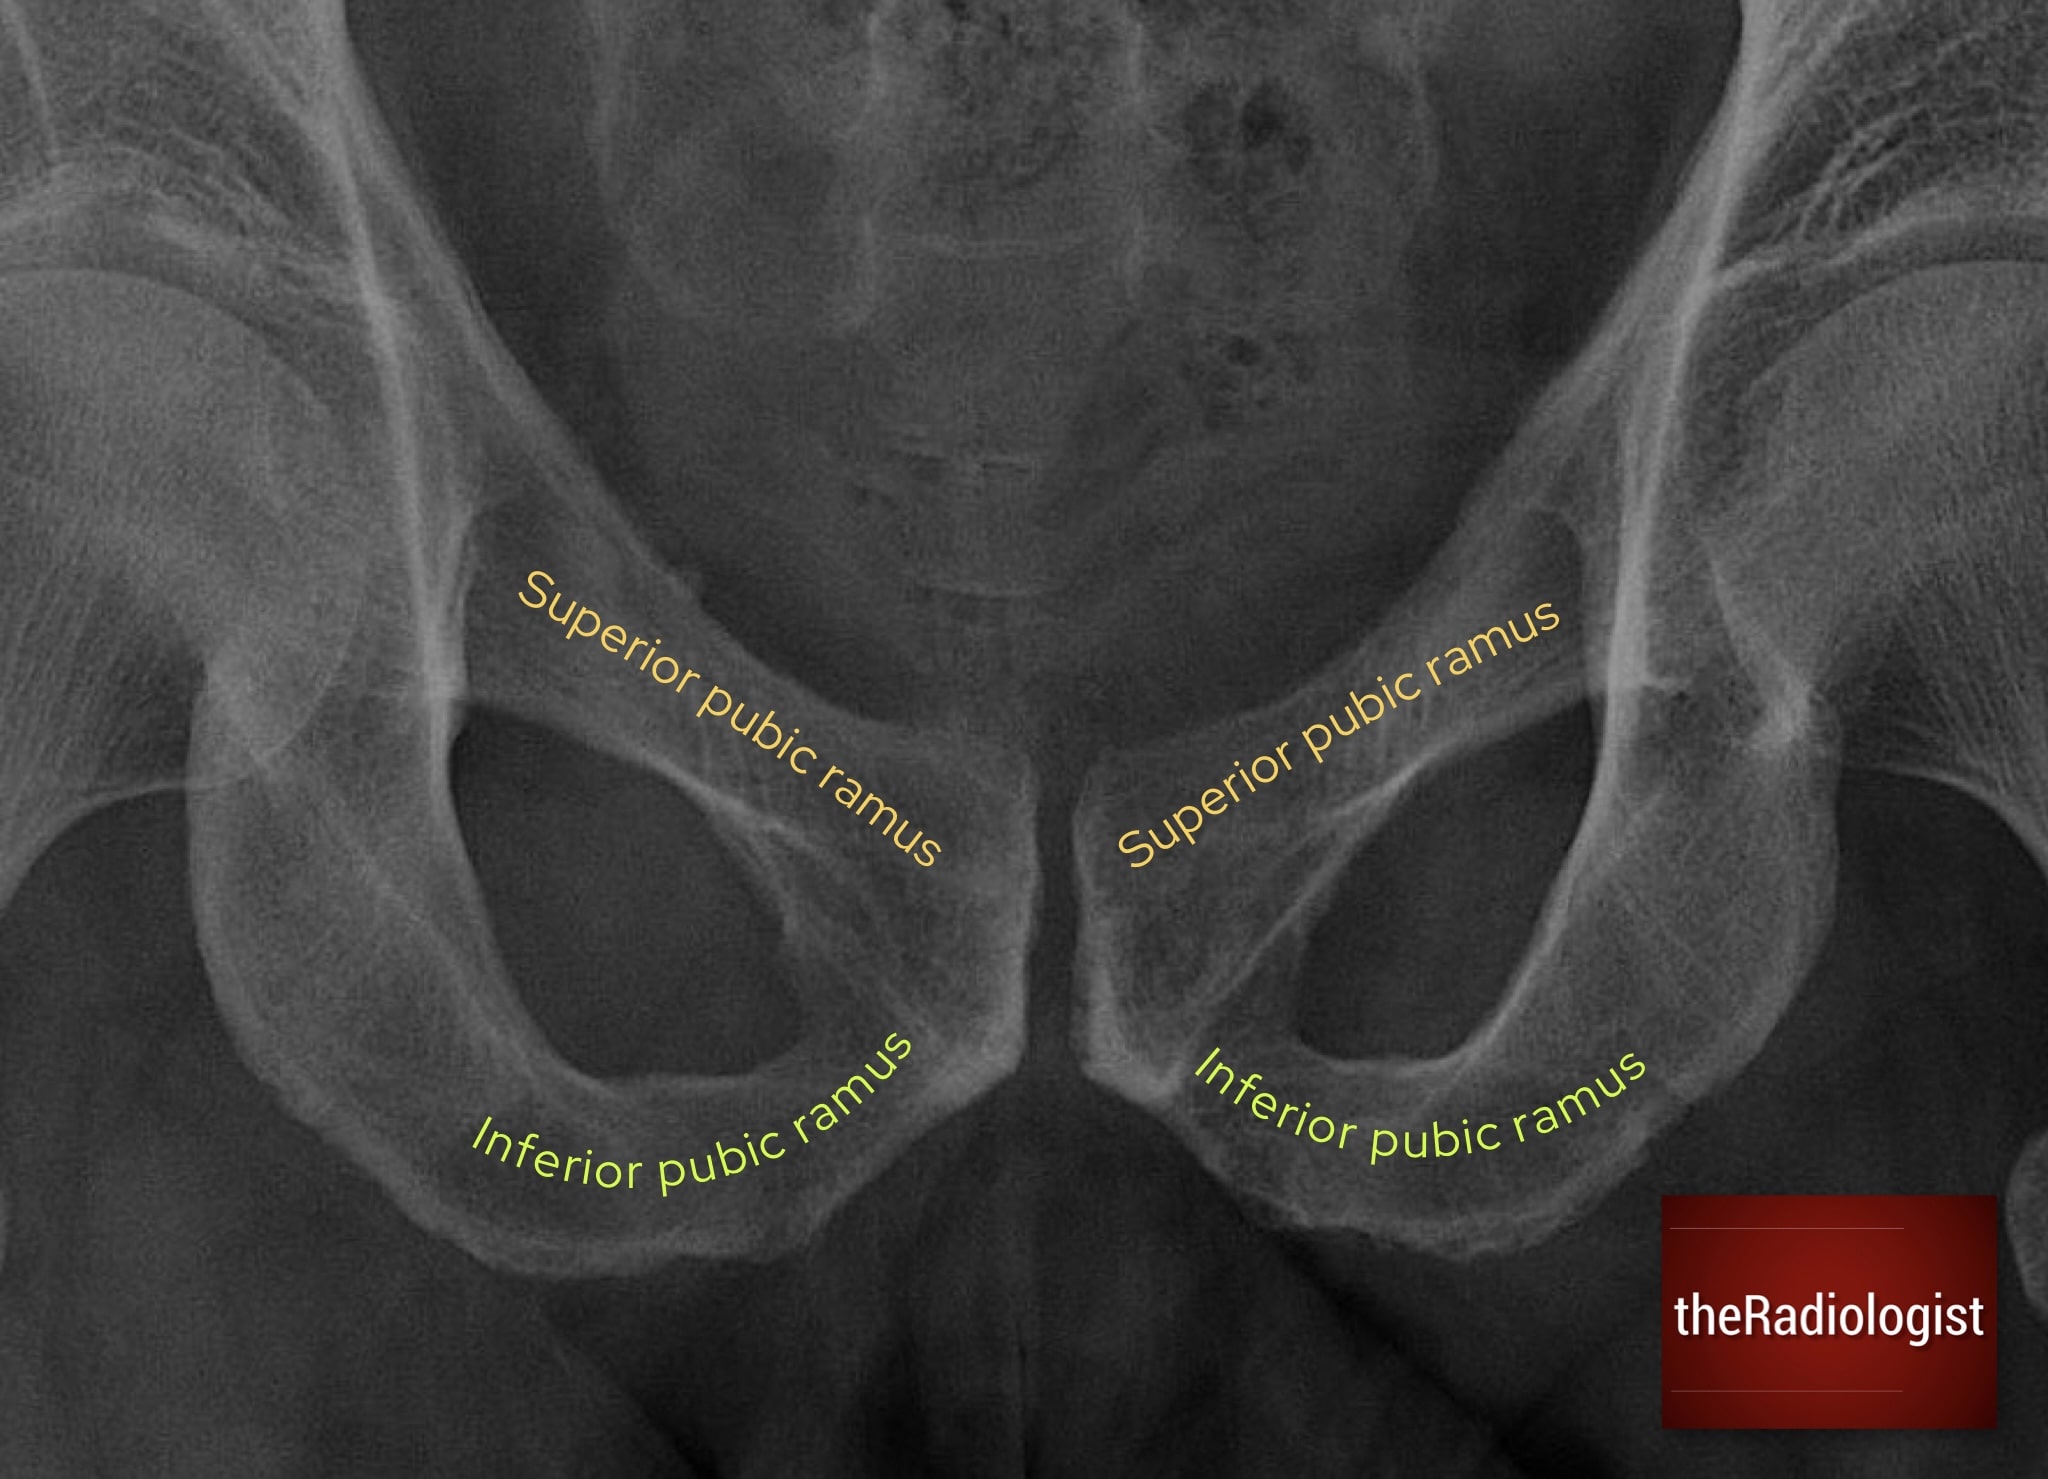

P: Pubic rami

Trace both superior and inferior pubic rami carefully. These are common fracture sites, especially in low-energy trauma in older patients. Fractures may appear only as faint cortical breaks or irregularities, so look carefully. Always compare both sides for symmetry, and remember: a break in one part of the ring usually means there is a second injury elsewhere.

Pay close attention to both the superior and inferior pubic rami looking for any subtle fractures.